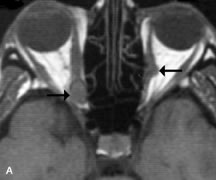

PATIENT PREPARATION Before MRI is performed, patients must be screened and prepared to avoid the potential hazards associated with the strong magnetic field. Patients who have ferrous aneurysm clips or cardiac pacemakers, who depend on life-support equipment, or who retain a possible metallic intraocular foreign body are not candidates for this imaging modality. MRI cannot be performed on obese patients who cannot fit into the bore of the magnet. Patients who are claustrophobic may not tolerate a prolonged period of study within the confines of the magnet, whereas others might do well if given a mild sedative. All worn metallic objects (e.g., necklaces, watches) should be taken off, credit cards set aside, and eye makeup removed before entering the room containing the magnet.5,20,34,35,36 NORMAL ORBITAL ANATOMY T1-weighted images provide the best anatomic details of the orbit because they display superior contrast resolution between normal structures (see Fig. 8). The vitreous has a long T1, resulting in an intermediate signal similar to brain, whereas the crystalline lens and sclera appear dark because of a longer T1 and short T2. The extraocular muscles, like all skeletal muscles, demonstrate a moderately long T1 and short T2 and highly contrast with the intense signal of the surrounding orbital fat (adipose tissue has an extremely short T1). The lacrimal glands appear as mottled areas of reduced intensity of the signal from the orbital fat in the lacrimal fossa. The optic nerves are seen with the same signal intensity as brain white matter and are hypointense relative to the orbital fat because their Tl is longer than the Tl of fat but shorter than the Tl of water. Cortical bone is not well delineated because it contains little free water, yielding minimal signal in MRI, and thus appears dark on all pulse sequences. This feature explains why MR images of the orbital apex and intracanalicular portion of the optic nerves are superior to comparable CT scans. Partial volume averaging of the bones in these regions obscures soft tissue details on CT images, whereas MRI reveals the signals only from the soft tissue structures with no cortical bone input. Bone marrow, on the other hand, is seen as a relatively intense signal because of its high fat content (see Fig. 8).37,38 T2-weighted pulse sequences are not ideal for imaging normal anatomy; however, they are particularly useful in revealing pathologic conditions (see Fig. 9). T2-weighted studies are most easily recognized by a bright vitreous signal. ORBITAL DISEASES Vascular Lesions Cavernous hemangiomas appear as well-circumscribed, smooth, usually intraconal masses that are isointense to muscle on T1-weighted images and hyperintense on T2-weighted images (Fig. 12). Patchy early enhancement is typically followed by diffuse, more homogeneous enhancement.39 The internal architecture of the mass, including septation and internal vasculature, may often be appreciated with high-quality orbital imaging.40 Lymphangiomas consist of ectatic vascular channels within a connective tissue stoma with varying degrees of lymphoid cellularity. On MRI, these tumors are typically poorly circumscribed, multicompartmental, and heterogeneous, often showing cystic dilations with fluid levels (Fig. 13). The signal characteristics within lymphangiomas vary considerably, reflecting cystic and solid components and the varying paramagnetic characteristics of blood at different stages of degradation.40–42 Acute hemorrhage appears hypointense on both T1- and T2-weighted formats. Methemoglobin present in subacute hemorrhage (3 to 14 days) leads to hyperintense signal on both T1- and T2-weighted images.41 A small percentage of lymphangiomas appear radiologically indistinct from orbital cavernous hemangiomas.43 Orbital varices are venous malformations that expand with increased systemic venous pressure, such as with Valsalva maneuvers. Because rapid acquisition of images during a Valsalva maneuver is important in imaging such a lesion, conventional or spiral CT is currently the modality of choice.44 MRI is an excellent modality for demonstrating enlargement of the cavernous sinus and dilation of the superior ophthalmic vein in patients with high-flow carotid-cavernous fistulas (Fig. 14).37MRA may be helpful in the evaluation of the venous outflow pattern. The rapidly flowing blood in these vascular structures carries the excited protons out of the section before they can be imaged, resulting in their dark appearance.5 In low-flow dural arteriovenous malformations, MRA may help define the arterial feeding vessels.45 Neural Lesions MRI is more effective than CT in delineating the intracranial optic nerves, chiasm, and optic tracts and, for this reason, is the preferred imaging modality in the evaluation of optic nerve disorders. The spatial relationships and image contrast of the orbital tissues with intraorbital optic nerve tumors is comparable between the two imaging modalities. The normal nerve is isointense to brain and appears enlarged and kinked owing to infiltration of an optic nerve glioma on T1-weighted images. Gliomas appear hyperintense on T2-weighted images and may be heterogeneous owing to cystic areas within the tumor. Contrast enhancement is variable.46 Intraorbital and intracranial optic nerve sheath meningiomas are usually isointense to cortical gray matter on Tl-weighted images and remain isointense on proton density studies (Fig. 15). Gd-DTPA is useful in delineating the intracranial extension of optic nerve meningiomas.7,47 The hyperostosis of bone and calcification associated with meningiomas are not demonstrated as well on MRI studies as on CT scans.20,37 Gd-DTPA–enhanced MRI also appears promising in the study of the permeability of the blood–brain barrier in selected optic neuropathies.22,48 MRI may reveal an enlarged optic nerve and some degree of contrast enhancement in cases of optic neuritis.49 Muscle Disorders Extraocular muscle enlargement in patients with thyroid-associated orbitopathy is demonstrated equally well with CT and MRI studies. However, the superior tissue contrast on MR images reveals better details of the relationships of the optic nerve to the thickened muscles at the orbital apex (Fig. 16).50 In addition, MRI may be able to differentiate between muscles that are enlarged as a result of edema and active inflammation and those enlarged because of fibrosis by their T2 relaxation times.21 Quantitative MRI was not found to be accurate in predicting the success of low-dose orbital irradiation.51 However, a muscular index relating the diameters of the rectus muscles to the bony orbital dimensions was useful in predicting optic nerve compression.52 MRI is also effective in imaging orbital tumors of mesenchymal origin, such as rhabdomyosarcoma, particularly in the assessment of extension into the anterior and middle cranial fossae (Fig. 17).37 The lack of any pathognomonic radiologic features necessitates rapid orbital biopsy when rhabdomyosarcoma is suspected. Osseous Lesions In general, CT is the imaging modality of choice when details of quantity and quality of bone are needed; however, abnormalities of bones can be detected indirectly by MRI. Cortical bone appears black (signal void) on MR images because of its low proton density and free-water content. The absence or discontinuity of the signal void of the orbital walls may represent bony destruction or fracture. Hyperostosis associated with prostate metastases or meningioma is visualized as areas of black smudging.50,53 Diseases in which the bone is replaced by pathologic tissues with a high free-water content, such as fibrous dysplasia, are well demonstrated on MRI. An intermediate signal intensity on T1-weighted images and hypointense signal on T2-weighted images is representative of fibrous dysplasia. Enhancement on post–Gd-DTPA MR scans is seen and is more evident in areas that are less mineralized.54 Cystic Lesions Dermoid cysts appear as rounded, well-defined lesions typically contiguous with an orbital bony suture. The high-intensity signal on T1-weighted images is attributed to the sebaceous-produced lipid contents (Fig. 18).31,50 Mucoceles may demonstrate a hypointense or hyperintense signal on MR images, depending on the concentration of proteinaceous or inflammatory fluid components. The integrity of the bony walls of the expanded sinus cavities cannot be assessed on MR as well as by CT.37,50,55,56 A high-signal intensity on Tl- and T2-weighted images is characteristic of orbital chronic hematic cysts because of the blood-breakdown products within the cysts.57 Trauma Although soft tissue relationships are usually better demonstrated on MRI, the evaluation of craniofacial bony trauma is preferable with CT. For example, prolapse of orbital fat through a fracture site and hemorrhage of adjacent tissues are demonstrated in an MR image, but the actual fractured bone is not imaged. Three-dimensional MRI of the orbit in subacute trauma has been described,58 although its precise role is not currently established. MRI has been suggested to be superior to CT in detecting intraorbital wooden foreign bodies.59,60 In a series of penetrating orbital injuries with organic foreign bodies, however, MRI was able to identify the foreign body in only four of seven cases.61 With an in vitro model for wood foreign body, McGuckin and colleagues concluded that CT was the imaging modality of choice.62 A careful history and, in selected cases, plain films to rule out a metallic foreign body are crucial before MRI is considered in patients with periocular trauma. MRI is particularly helpful in the detection and characterization of subperiosteal hematomas of the orbit (Fig. 19). They are most commonly seen in the subperiosteal space of the superior orbit as well-defined masses following a traumatic injury. The signal intensity varies depending on the acute, subacute, or chronic nature of the hematoma, based on the stage of blood degradation. Fresh hemorrhages are hypointense on T1-weighted images and hyperintense on T2 images. Hematomas that are 1 to 7 days old are hypointense on both T1- and T2-weighted images. T1-weighted images of hematomas more than a week old are hyperintense due to the oxidation of deoxyhemoglobin to methemoglobin, whereas the T2 images remain hypointense.63 Metastatic Tumors Breast carcinoma metastatic to the orbit has been demonstrated to be hypointense to the surrounding orbital fat on T1-weighted studies and hyperintense on T2-weighted images and has an affinity to the extraocular muscles (Fig. 20).50,64 The MRI characteristics of prostate carcinoma metastatic to the orbit have been described as involving the greater and lesser wing of the sphenoid, orbital roof, and optic canal. Diffuse bone hypertrophy with isointense or slightly hyperintense tissue on T1-weighted images represents the osteoblastic carcinomatous bone infiltration. Contrast enhancement is variable on T1-weighted and fat-suppressed images.65 Most other metastatic tumors also have a lower intensity signal on T1-weighted images and appear to displace or infiltrate normal orbital structures; however, their signal characteristics are variable on T2-weighted MR images.66 Many metastatic tumors demonstrate bright contrast enhancement with Gd-DTPA. Infectious Disorders MRI findings of preseptal and orbital cellulitis typically include increased signal intensities on T2-weighted images of the eyelids and orbital fat, respectively, due to the increased water content of the tissues. Since most cases of bacterial orbital cellulitis are associated with paranasal sinusitis, hyperintense signals of the affected sinuses may also be found on T2-weighted images as well as enhancement of polyps and granulation tissue on postgadolinium T1-weighted MR images. Subperiosteal abscess formation may occur due to contiguous spread of infection from the paranasal sinuses and appear on MRI as an area of intermediate signal on T1-weighted and proton-weighted MR images. The abscess may appear slightly hyperintense compared with muscle on T2-weighted scans with the necrotic contents having the greatest intensity.67 MRI and MRV are more sensitive than CT in revealing cavernous sinus thrombosis. Engorgement of the cavernous sinus, extraocular muscles, and ophthalmic veins is seen with hyperintensity of the thrombosed sinuses evident on all pulse sequences. The enlarged, thrombosed superior ophthalmic vein appears less hypointense than the normal contralateral ophthalmic vein, and hyperintensity within the lumen of the vessel may be seen on T1- and T2-weighted MR images.68 Inflammatory and Lymphoproliferative Lesions Inflammatory conditions of the orbit, both idiopathic (inflammatory pseudotumor) and those of known causes, have been found to be hypointense to fat and isointense to muscle on Tl-weighted studies and isointense or slightly hyperintense to fat on T2-weighted images (Fig. 21).50,64,69 The more fibrous or sclerosing varieties have less signal intensity on T2-weighted images. Marked enhancement is seen in pseudotumor infiltrates after gadolinium administration.70 The same signal characteristics are demonstrated in patients with Tolosa-Hunt syndrome, with mass lesions seen in the cavernous sinuses and orbital apices.71 Lymphomas have MRI characteristics similar to those of inflammatory lesions in that they are hypointense to fat and isointense to muscle on T1-weighted images (Fig. 22). They may appear hyperintense to fat on T2-weighted images, perhaps owing to less fibrosis than that seen in orbital inflammatory pseudotumor, although this is not a consistent finding.31,50,66 Lymphoid tumors typically enhance moderately after contrast injection. Unfortunately, studies have shown that tumor density and homogeneity are similar between inflammatory and malignant orbital infiltrates, and MRI cannot differentiate these lesions.72,73 Lacrimal Gland Tumors Lacrimal gland lesions present special problems in diagnosis and management. Pleomorphic adenoma (benign mixed tumor) should not be biopsied, but rather excised in toto. On the other hand, for lymphoma and inflammatory infiltrates, incisional biopsy is more appropriate than complete excision of the lacrimal gland. Thus, preoperative clinical and radiologic evaluation are especially crucial in planning appropriate surgical management. Pleomorphic adenomas demonstrate long T1 and T2 signal characteristics. They may show heterogeneity on T2-weighted images74 and moderate to marked enhancement with contrast.75 Signal characteristics of adenoid cystic carcinoma include hypointensity to fat on T1-weighted images, hyperintensity to fat with increased T2 weighting, and isointensity to fat on proton density-weighted studies (Fig. 23).31,75 Secondary bony alterations of the lacrimal fossa associated with lacrimal gland tumors, such as remodeling (benign mixed tumor) or destruction (adenoid cystic carcinoma), are seen indirectly on MR images; however, bone windows on CT scans provide better delineation of these changes. In contrast to the round or globular appearance of benign or malignant epithelial tumors of the lacrimal gland, lymphoproliferative tumors usually appear to be molding or draping onto the globe and the surrounding bony orbit. LACRIMAL DRAINAGE SYSTEM DISORDERS MRI with surface coils provides excellent spatial resolution and tissue-specific signal intensities of the lacrimal drainage system. These parameters have been found useful to more accurately demonstrate the extent of lesions in the lacrimal sac and differentiate long-standing mucoceles from solid tumors than CT.76 Physiologic studies in patients with tearing disorders now include MR dacryocystography, in which Gd-DTPA is either placed topically in the conjunctival fornix or injected by cannulation into the lacrimal sac. They provide a detailed morphologic and functional analysis of the lacrimal excretory system; however, they are no more sensitive than digital-subtraction dacryocystography or CT dacryocystography.77–79 INTRAOCULAR TUMORS On MRI, uveal melanomas have a typical appearance that helps to differentiate them from other primary and secondary intraocular tumors as well as choroidal detachments. Pigmented melanomas are hyperintense on Tl-weighted images, hypointense on T2-weighted studies, and hyperintense on proton density–weighted examinations (Fig. 24).30,31,50,80–82 These signal characteristics have been attributed to the paramagnetic properties of melanin because of stable free radicals that shorten the T1 and T2 relaxation times. Moderate enhancement is seen on postgadolinium T2-weighted images. Gadolinium-enhanced T1-weighted images are particularly sensitive in detecting choroidal melanomas.83 MRI may be less sensitive in detecting extrascleral extension of tumor than echography performed by an experienced ultrasonographer.84 Tumors metastatic to the choroid are hyperintense on T1- and T2-weighted images.24 The signal characteristics, however, may be similar to those seen with choroidal melanoma. Choroidal hemangiomas, on the other hand, have an intermediate signal on T1-weighted sequences and become hyperintense on T2-weighted images50 as well as proton density–weighted images.81 Retinoblastomas display moderate signal intensity on T1-weighted studies and a low signal on T2-weighted images.31,80,85 Calcification can be easily detected by CT and ocular ultrasonography but is not imaged by MRI.25,50 The presence of optic nerve involvement is best evaluated by MRI. ACQUIRED ANOPHTHALMIA When an eye is removed owing to tumor or trauma, an implant is typically placed in the intraconal space. MRI may be useful in defining the size, shape, and position of such orbital implants.86 Porous hydroxyapatite or polyethylene implants are preferred by many surgeons performing enucleation or evisceration. A porous implant offers the possibility of supporting a motility coupling peg to increase the movement of the overlying prosthesis. MRI with contrast is used by some surgeons to evaluate the degree of fibrovascular ingrowth in hydroxyapatite87 and porous polyethylene88 implants prior to motility peg placement. |